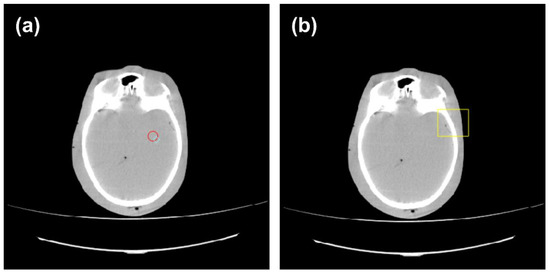

3.4. Impact of Bilateral Filter on Anthropomorphic Images